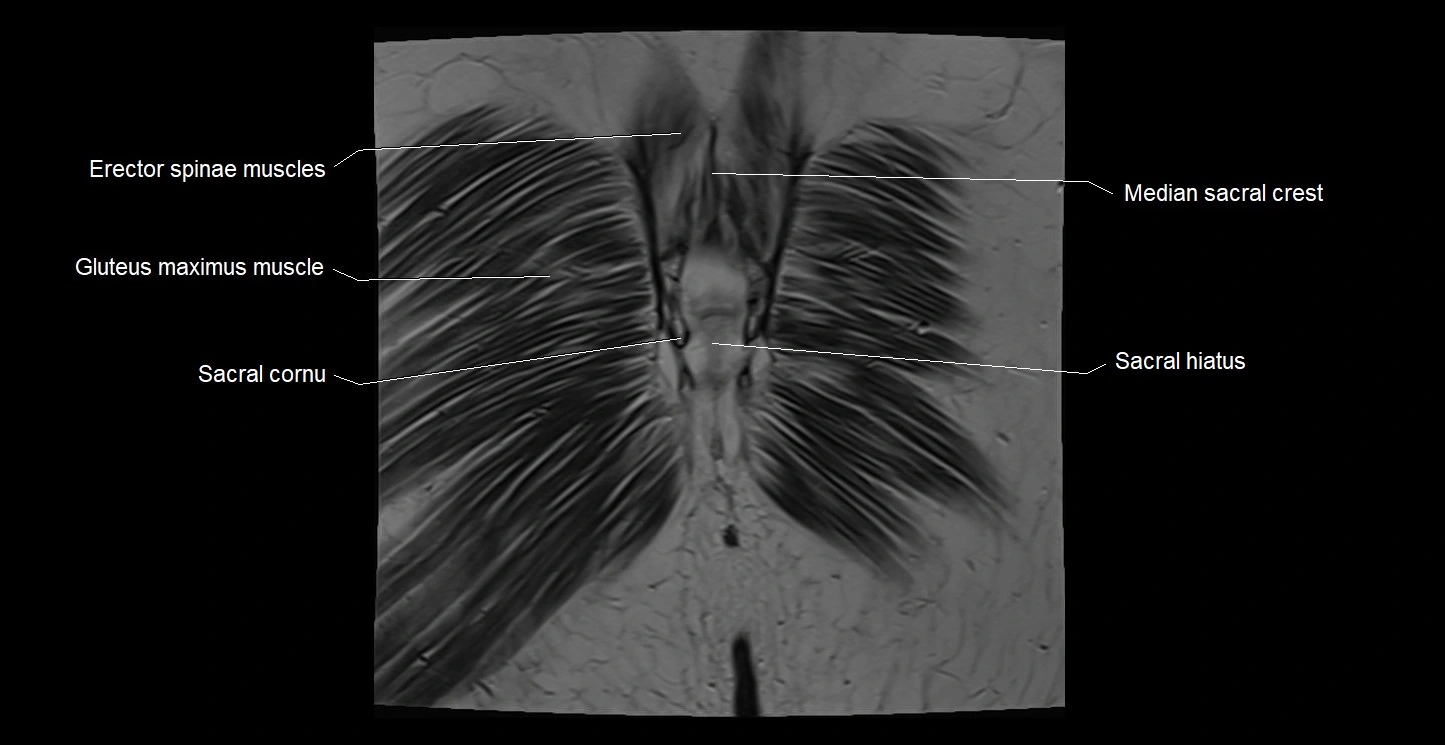

- Erector spinae muscles

- Gluteus maximus muscle

- Median sacral crest

- Sacral cornu (sacral horn)

- Sacral hiatus